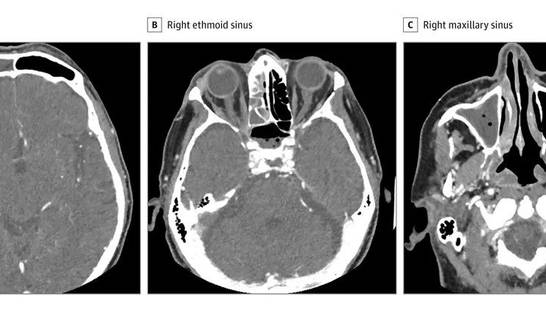

Коронавирус влияет на нервы роговицы